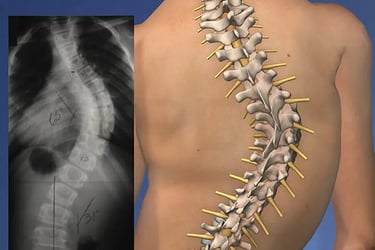

La escoliosis es una condición en la que la columna vertebral se curva de manera anormal, a menudo formando una "S" o una "C" en lugar de estar recta. Aunque algunos casos de escoliosis son leves y no causan problemas significativos, otros pueden generar dolor, incomodidad e incluso dificultar el movimiento y la postura. Comprender los síntomas, las causas y los tratamientos disponibles para la escoliosis es esencial para gestionar esta condición y mejorar la calidad de vida.

La escoliosis es una condición caracterizada por una curva anormal en la columna vertebral, que puede ocurrir a cualquier edad, pero se diagnostica comúnmente durante la niñez o la adolescencia. La curvatura puede variar desde leve hasta severa y generalmente se desarrolla a medida que la columna crece. En algunos casos, la escoliosis puede empeorar con el tiempo, lo que provoca más incomodidad, restricción de movimiento y, en casos graves, problemas respiratorios.